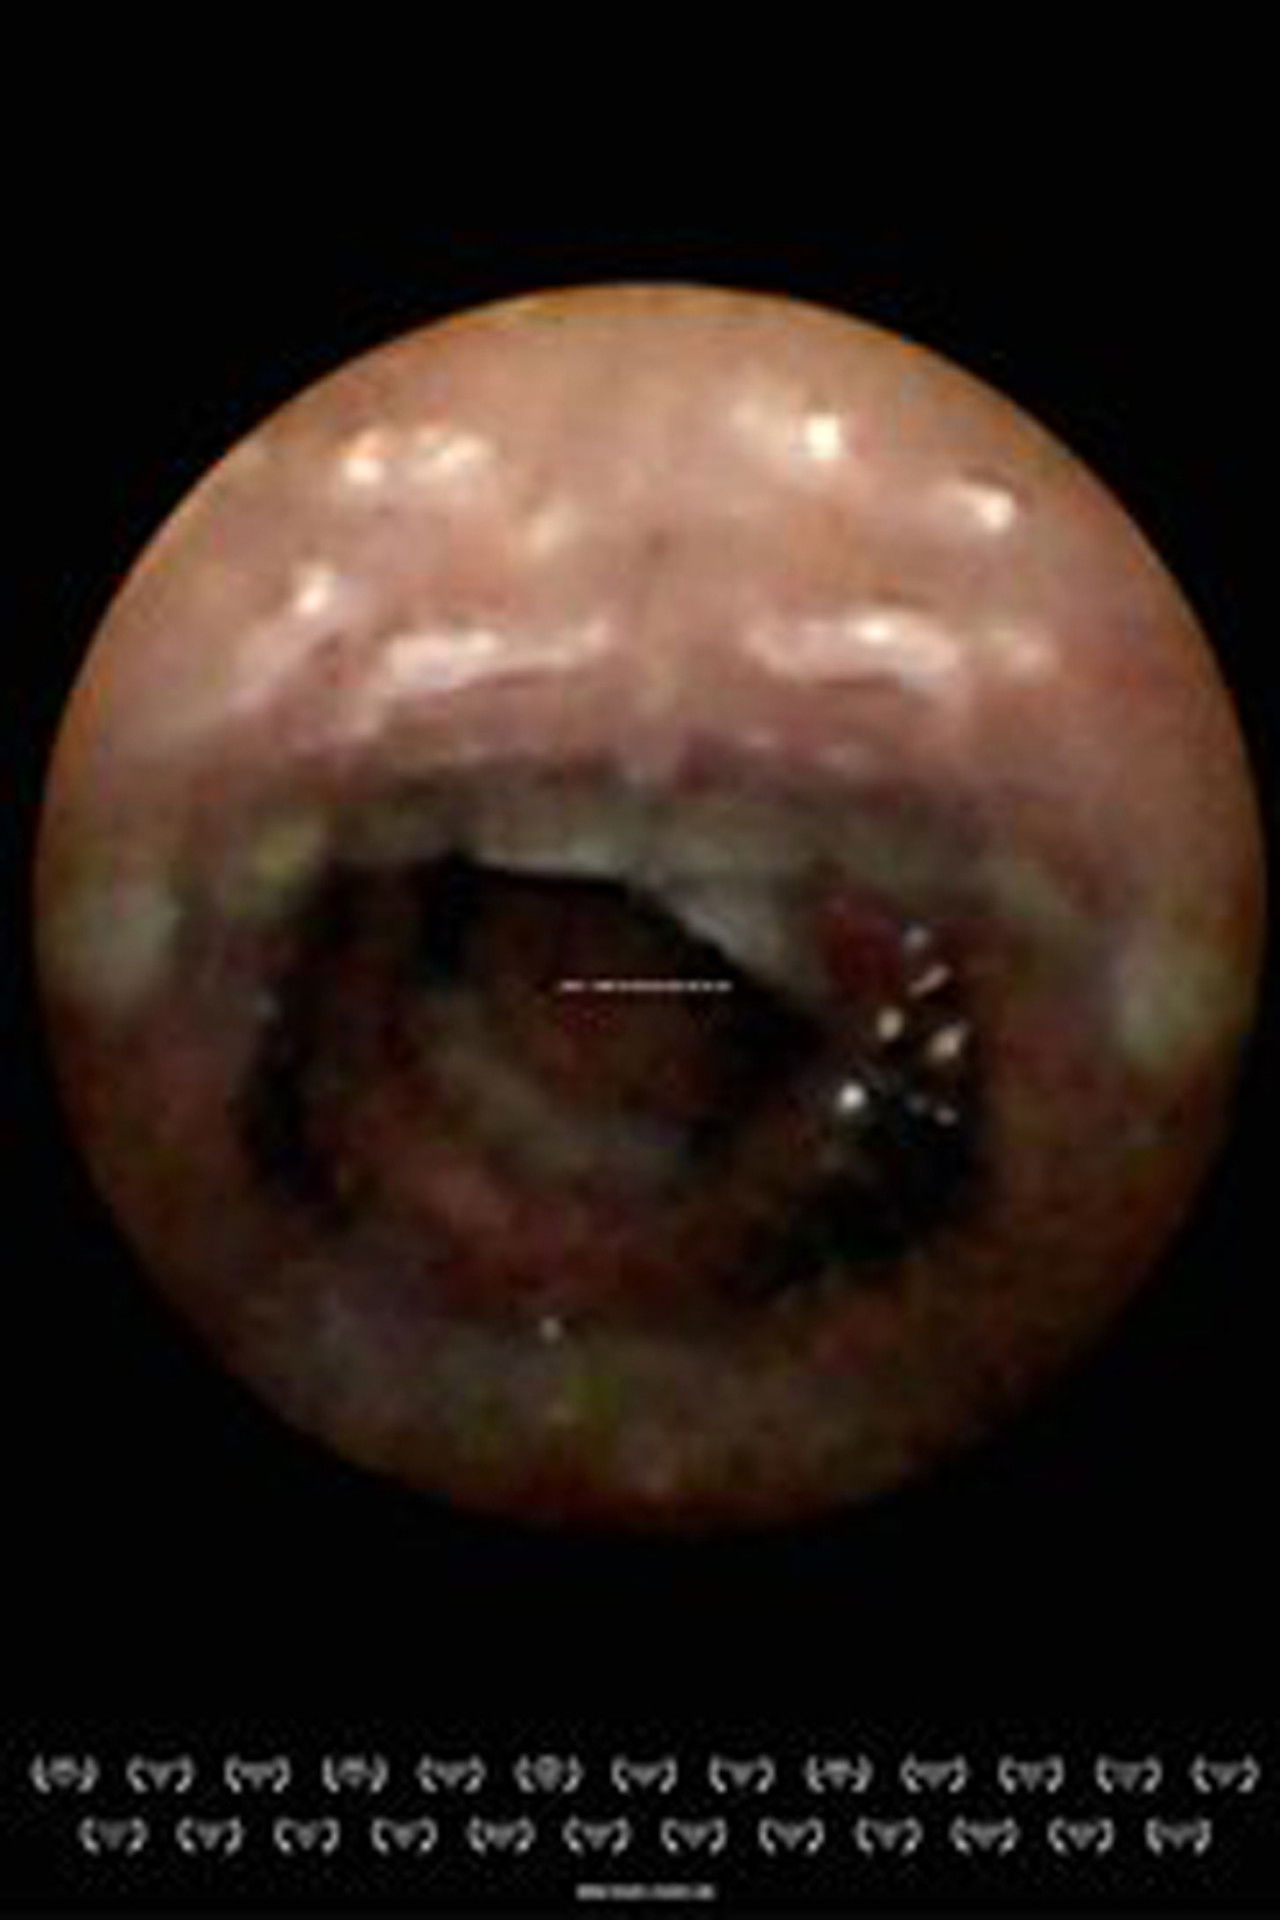

We want it. We buy it. We eat it. We swallow it down whole. But what does our body see when we stick it in our mouth?